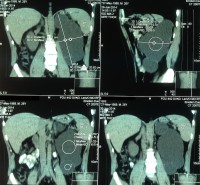

ОПУХОЛЬ ПОЧКИ19.11.14